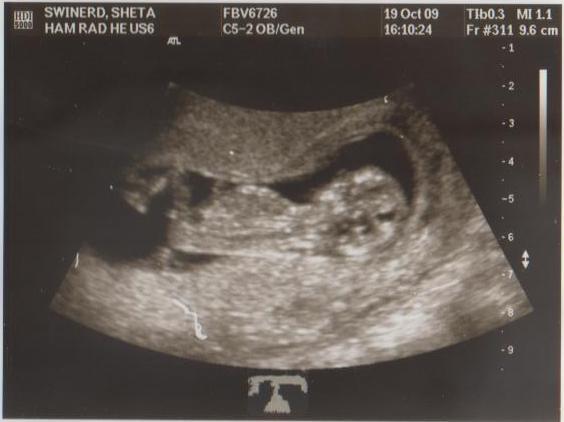

Last week I had a scan to tell me everything was ok with my pregnancy. So, now I can announce to those who are interested, this is the reason I haven’t been on stage this season. My slight weight gain, expanding waist line and bigger boobs have raised a few eyebrows of concern; some people thought I was simply ‘enjoying the married life’ but the real reason is a lot better!

Last night I was craving oats! OMG – will I actually be able to handle my tasty breakfast!? The next day I wake up feeling completely energised, and feel like my regular self – full of energy and ready to attack the day. I make oats for brekky and love them. I even feel like a good training session…but today is fully booked up to the point where I have to down a litre of water (not pee it out for an hour) before my scan. I eat super healthy all day; ‘normal’ food again! The scan is a success and I plan to train tomorrow if I feel this good.